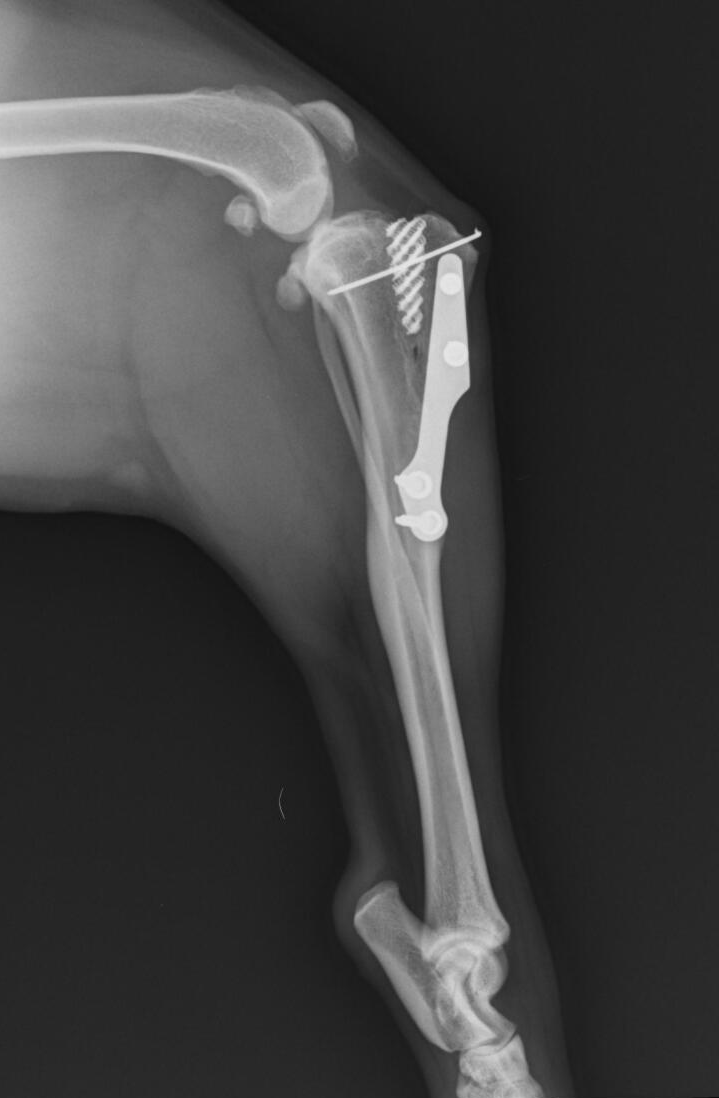

Cirugía

Quirófano dotado con equipo anestésico de última generación, monitorización y personal ampliamente cualificado en cirugía.